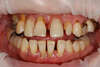

5- Résolutions de problèmes combinés par les implants

Ce patient présente la combinaison de plusieurs problèmes : infections, déchaussement dentaire, caries et dents absentes.

Après une phase d'assainissement et la mise en place de prothèses provisoires, une simulation en 3 dimensions de la situation est réalisée

Une étude avec simulation informatique permet de planifier précisément la pose des implants

Les implants sont alors installés et une prothèse implanto-portée est fixée en bouche 48 heures après.

Après cicatrisation, les prothèses définitives peuvent être réalisées